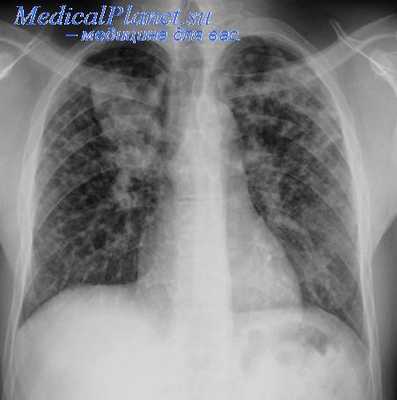

плевральный выпот на рентгеновском снимке